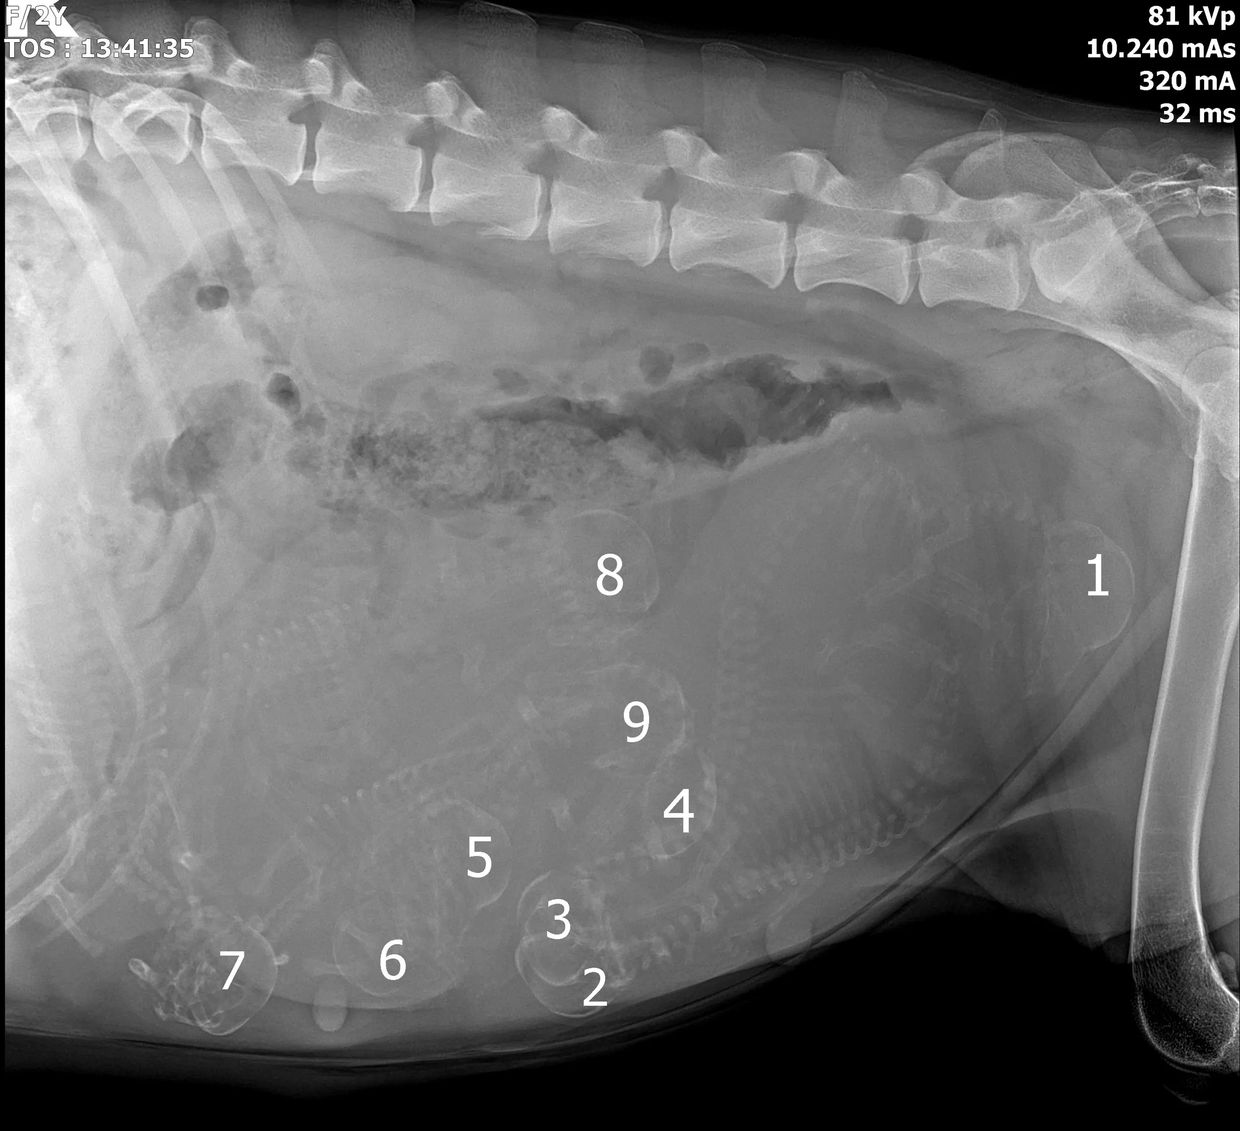

Dr. Cindy made out 9 pups on the xrays!! She counted 10 on the ultrasounds, but counting on ultrasounds is really hard and inexact.

Maybe another one is hiding, maybe not. Either way, 9 pups is a lot for a first time mom.